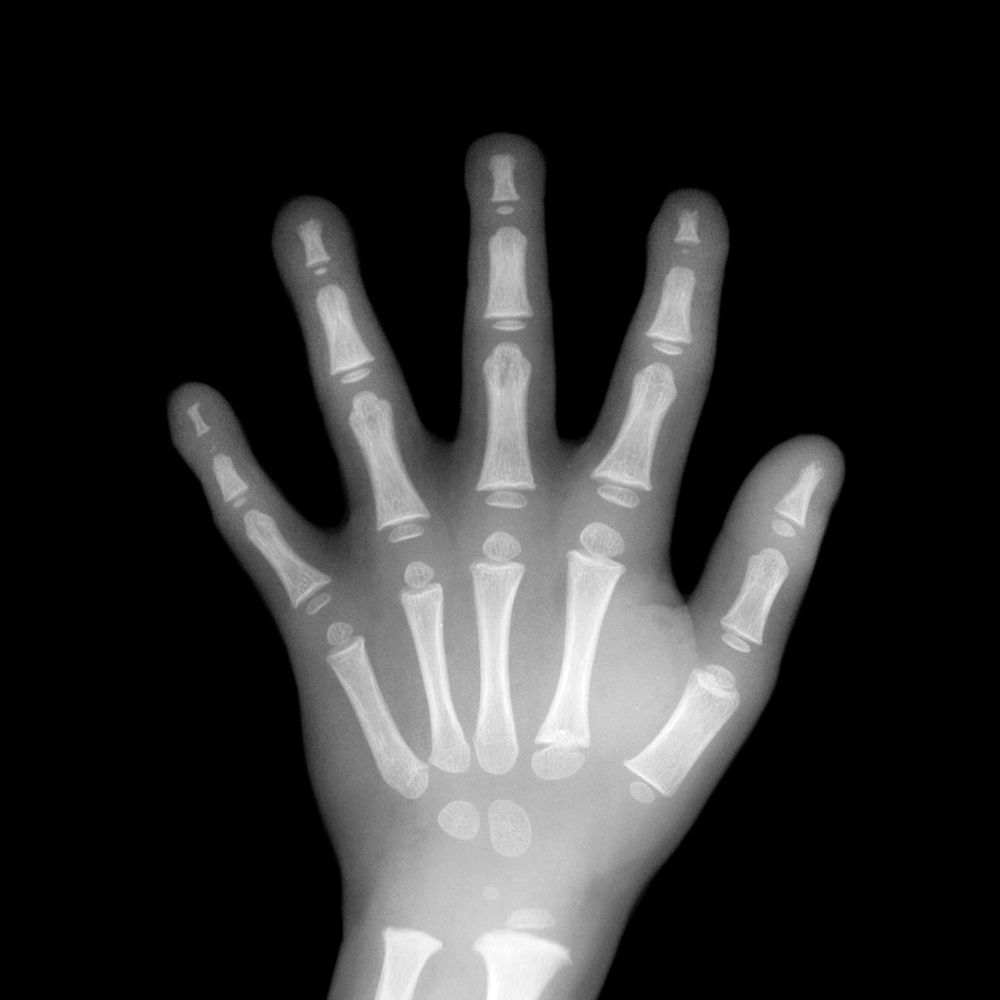

손 X-ray 기반 AI 골연령 분석으로 성장판 상태를 확인하고, 최종키 예측까지 수치로 계산합니다.

손 X-ray 및 AI 분석으로

골연령을 산출하고, 이를 종합해

최종 성장 예측치를 계산합니다.